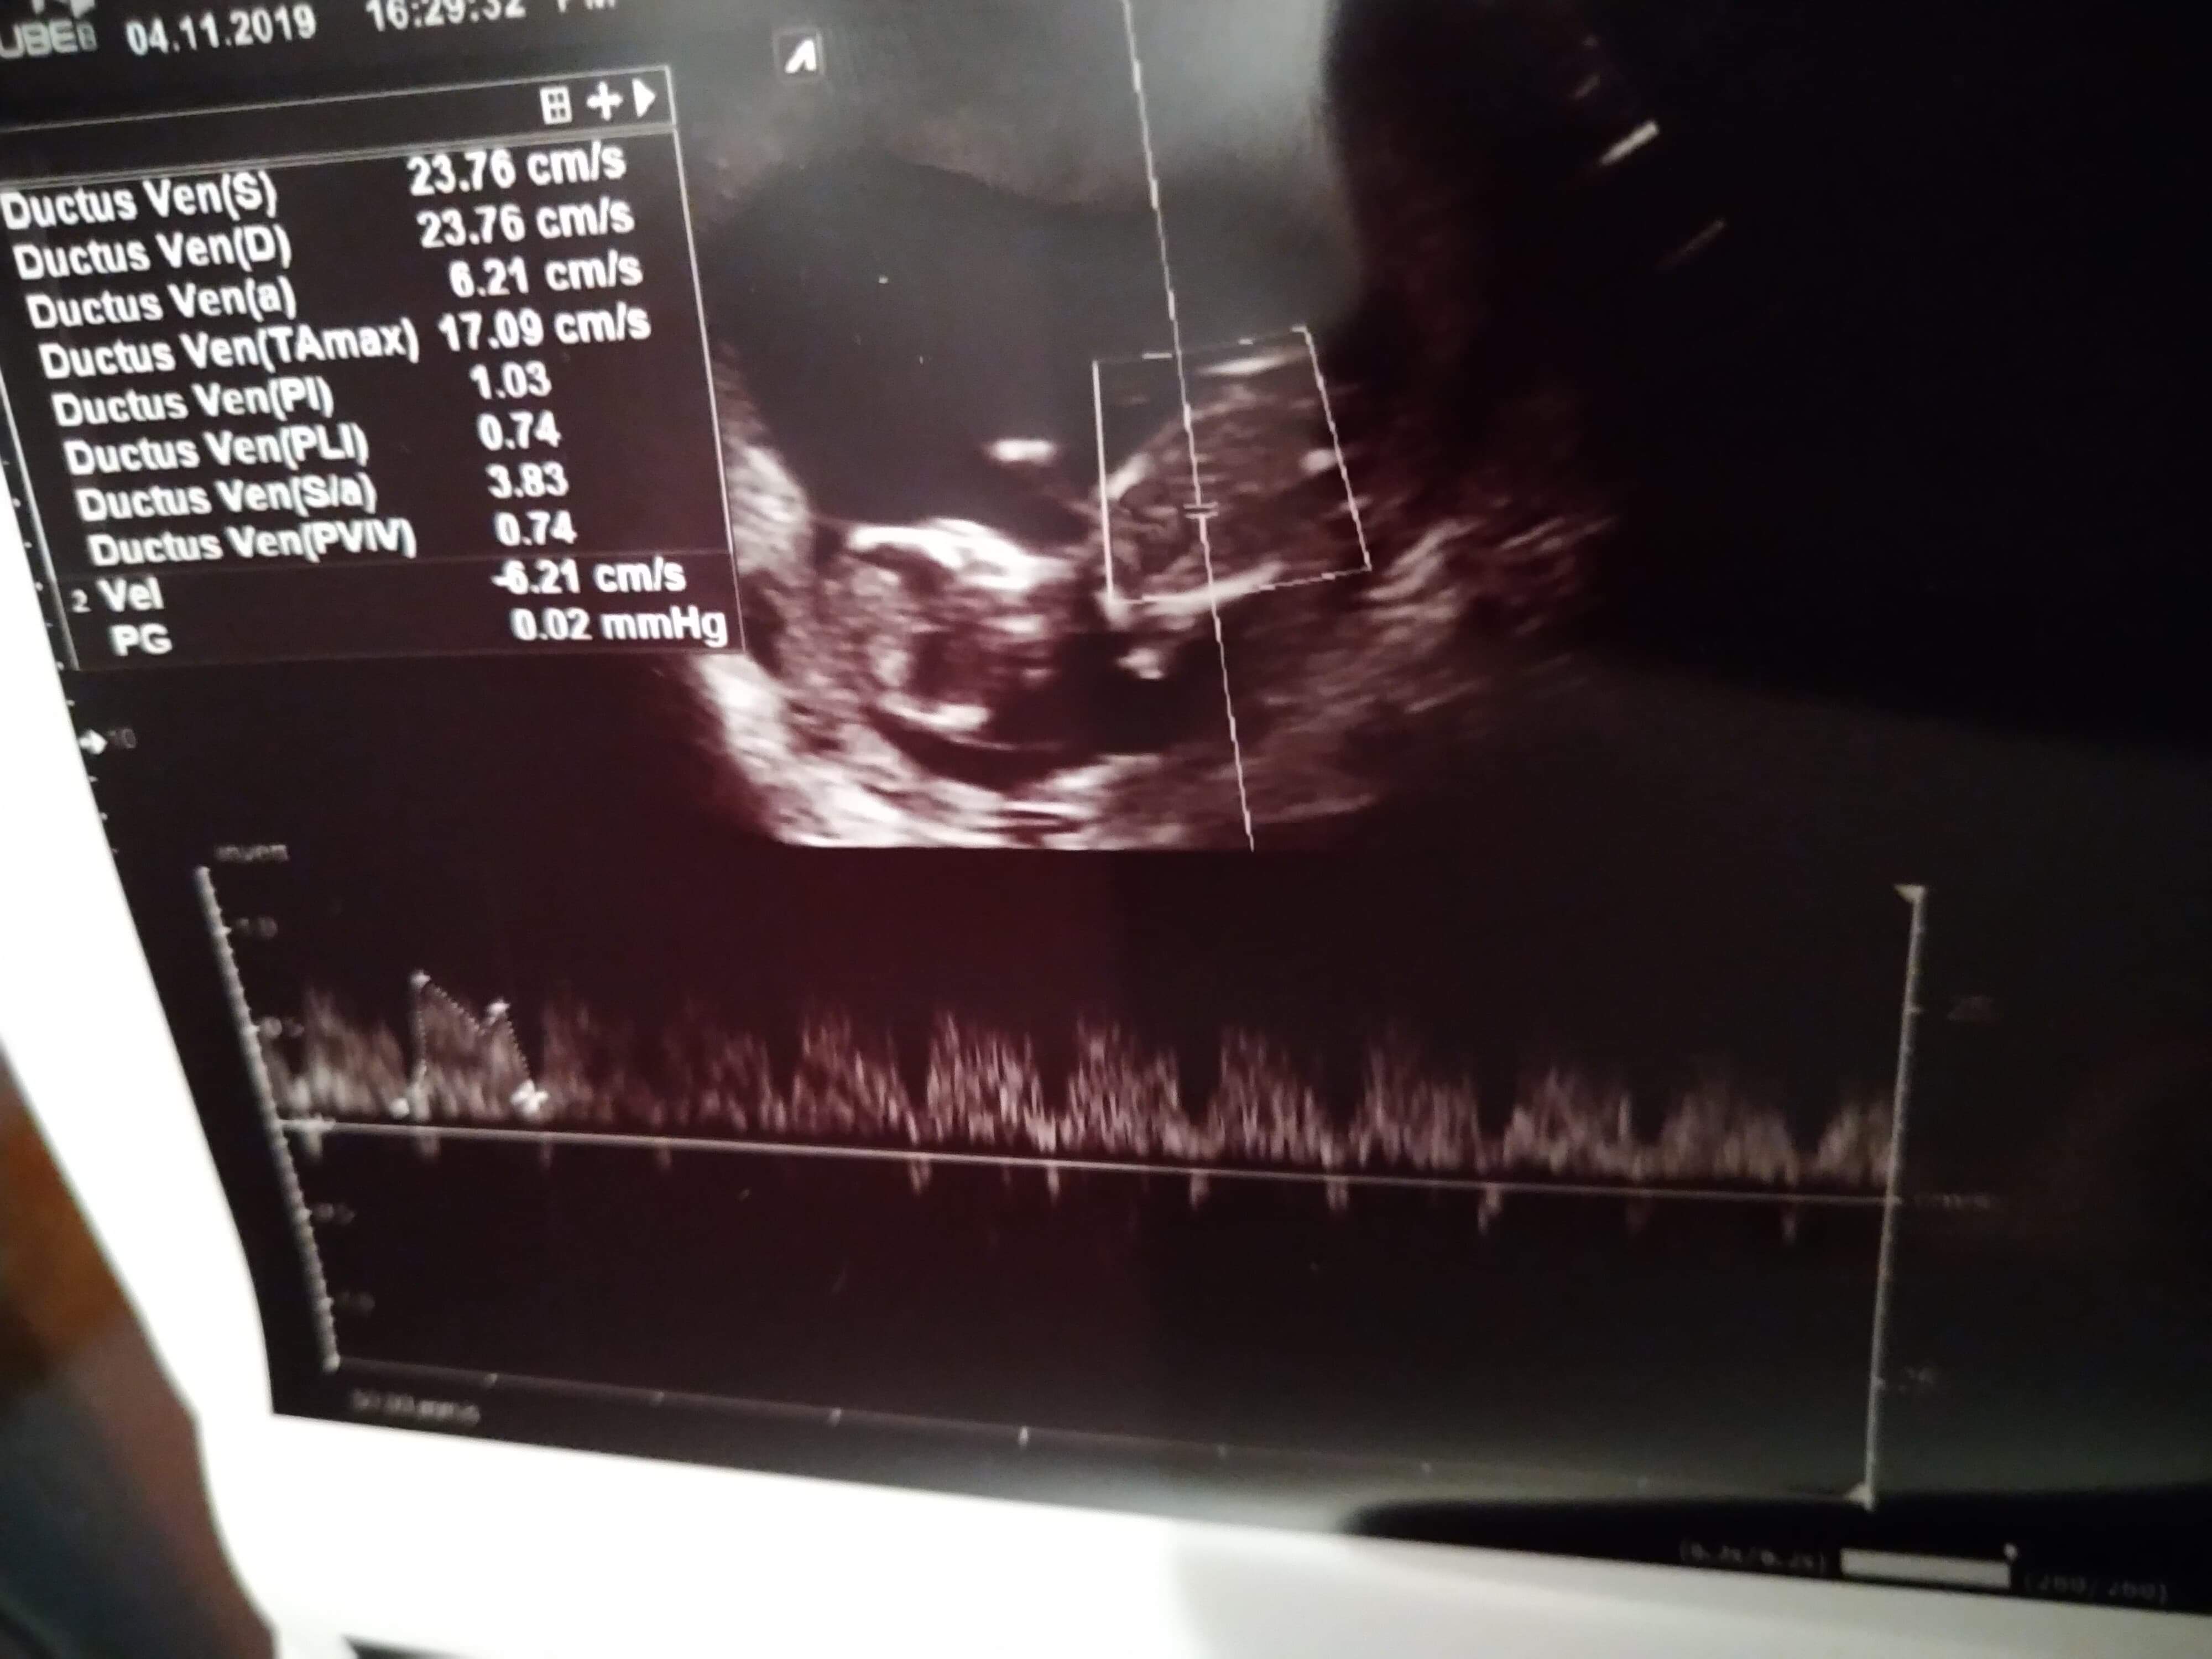

Dziecko ma 6,3 cm. Z USG 12+5, termin 13.05. Z OM 12+4, termin 14.05. Przezierność karkowa 1,04. Tętno 175/min. Nosek jest, rączki nóżki również. Mózg prawidłowo i serducho również. Dziecię jest bardzo ruchliwe i wiercące się. Do tego uparte i charakterne po rodzicach. Nie chciało dać się zmierzyć, ani obrócić z boczku i pokazać. A jak już zaczęło się obracać to tak szybko, że nie dało się nic zmierzyć i ocenić.